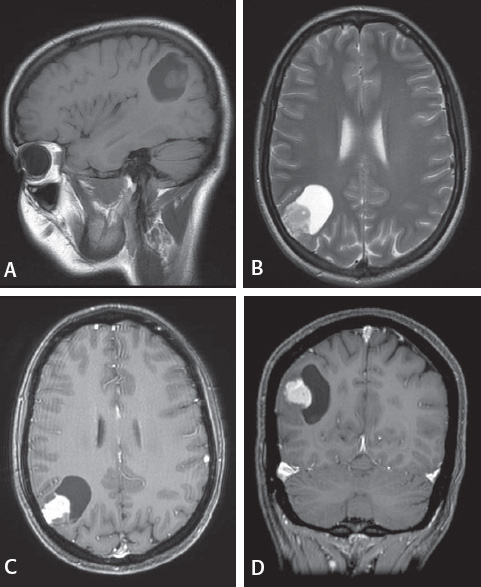

Magnetic resonance imaging characterized the lesion as a single 3.5 x 3.7 x 2.6 cm intraparenchymal mixed solid and cystic mass lesion located wi thin the right parietal lobe. There was no peri-tumoral associated vasogenic edema or necrosis, nor was there ring enhancement of the cystic portion of the mass. The solid component followed iso T1 and T2 signal, and enhanced

avidly post gadolinium infusion. (Figure 1)

Figure 1

(A)

Sagittal T1 image without gadolinium. (B) Axial T2 image. (C) Axial T1 post gadolinium. (D) Coronal T1 post gadolinium. Both gadolinium images show avid enhancement of the solid portion of the mass lesion.